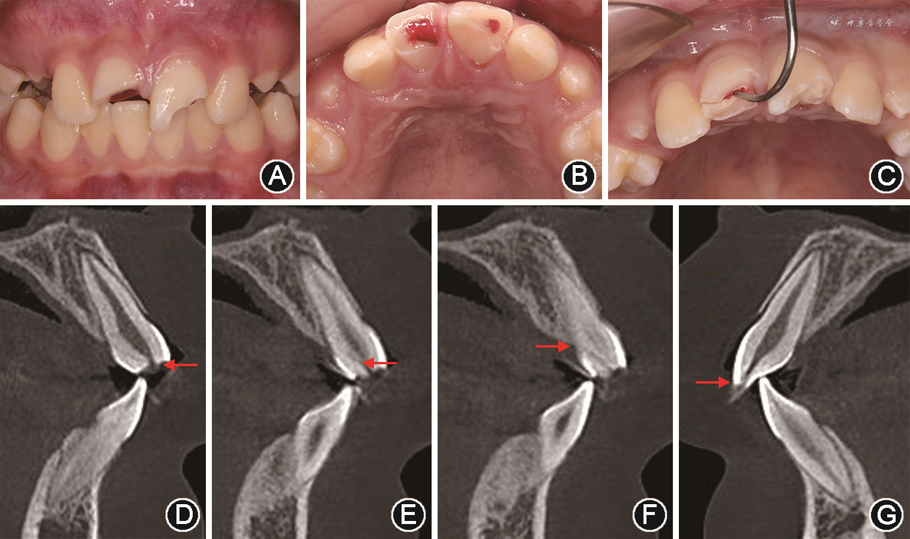

(7)术后随访:术后6个月复查见21因再次外伤导致牙冠切端缺损(图3A),11、21无不适症状,腭侧探无牙周袋(图3B),根尖片示根尖周均无明显异常(图3C);因21牙体缺损较少,于缺损唇腭面分别制备固位沟(图3D),采用37%磷酸酸蚀粘接及复合树脂充填修复牙冠形态(图3E)。术后12及24个月复查,11、21无不适症状及阳性体征,断冠粘接及充填物完好,咬合功能正常(图3F,G),根尖片示11根充密实、根尖周无低密度影像(图3H),但切髓24个月的21表现出明显的根管闭锁(图3I);11、21牙周探诊均无牙周袋,牙龈色泽正常、致密,11腭面探及连续完整稳定的牙周附着(图3J)。

像;B:术后6个月11、21

面像;C:术后6个月11、21根尖片;D:21再次外伤牙冠修复过程口内像;E:21再次外伤牙冠修复后口内像;F:术后12个月正面

像;G:术后24个月正面

像;H:术后12个月11、21根尖片;I:术后24个月11、21根尖片,显示根管闭锁;J:术后24个月11

面像示腭侧牙周健康,未及牙周袋

面像示腭侧牙周健康,未及牙周袋复杂冠根折在牙外伤中并不罕见,但当其折裂线延伸至牙槽嵴顶水平以下时,治疗难度增大,常涉及多学科联合治疗,包括口腔外科、牙体牙髓、正畸、修复及影像学等[9],通常是由儿童口腔医师确定治疗计划,并在全程行为管理下完成治疗。